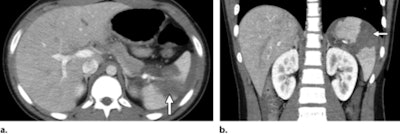

- Abdominal: Pancreas, small bowel, mesentery, liver, spleen, adrenal gland (liver lacerations may present as linear hypoattenuating lesions; spleen lacerations range from linear to branching patterns)

- Pancreatic: Contusion and inflammation ("focal or diffuse enlargement of the pancreas with decreased enhancement and associated peripancreatic fat stranding and fluid")

- Duodenal: Hematomas (may visualize as "an intraluminal, intramural, or paraduodenal collection with increased attenuation"), perforations, lacerations ("interruption of the enhancing bowel wall, extravasation of intraluminal contents, or free retroperitoneal air")